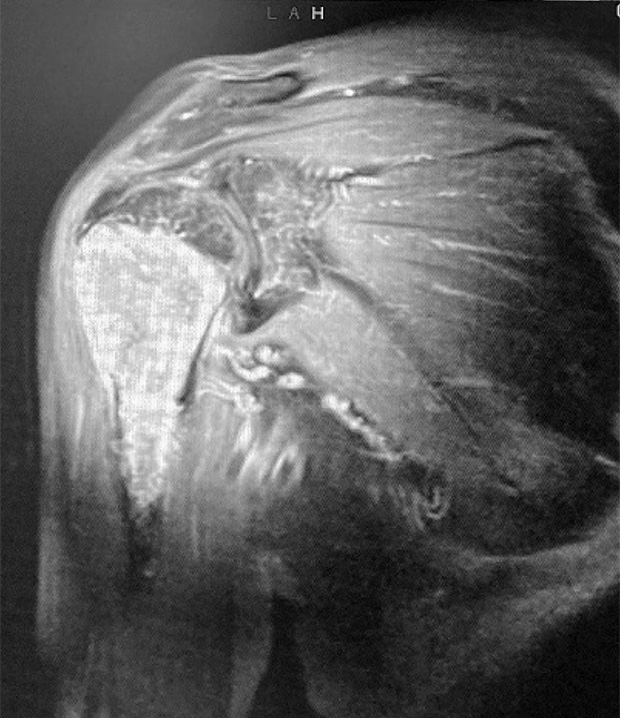

Pre-op

Pictures 1 and 2: X-ray a-p and MRI

Patient:

- 73 year old male with bone tumor in the proximal humerus right side